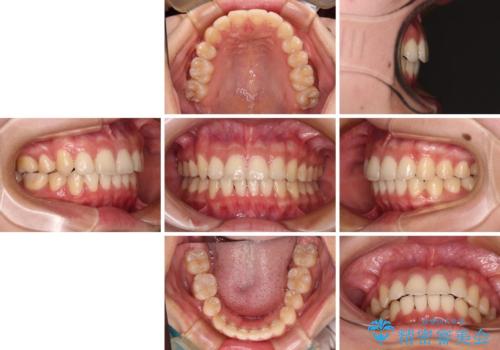

骨格的に下顎が左側に変位していたため、上下正中を合わせることは困難であることは分かっていましたが、可能な限り合わせることができました。

骨格的なズレがあると仕上げの段階で奥歯の咬み合わせが不安定となるため、予定よりやや長期間となりました。